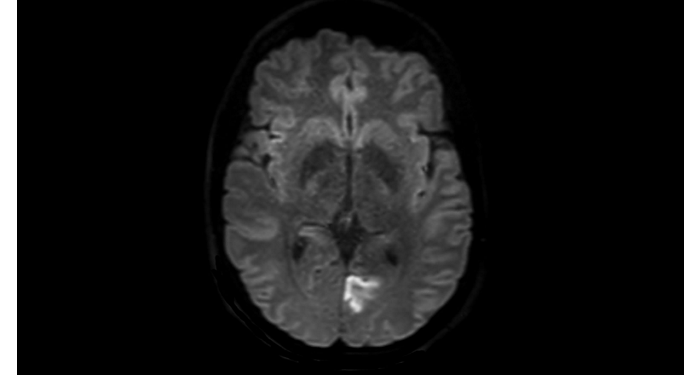

Hospital Eramse, Bélgica

Imágenes de la IRM de campos oscuros de un paciente con VIH con vasculitis cerebral

Las imágenes de campos oscuros ayudaron a sugerir el diagnóstico y elegir el tratamiento.